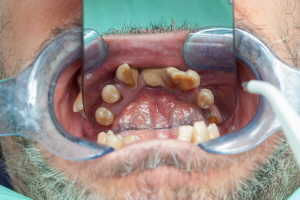

임플란트 건강보험 적용 조건

앞서 임플란트는 비급여 항목이라고 설명드렸지만, 일정 조건을 충족하면 건강보험 혜택을 받을 수 있습니다. 이 경우 비용을 크게 절감할 수 있는데요, 건강보험 적용 대상과 조건을 알아보겠습니다.

건강보험 적용 조건

- 만 65세 이상인 경우

- 건강보험 가입자 또는 피부양자여야 함

- 일부 치아가 남아있는 경우에 한해 적용 가능

이 조건을 충족하면 평생 임플란트 2개까지 건강보험이 적용됩니다. 다만, 완전히 치아가 없는 경우에는 건강보험 혜택을 받을 수 없습니다.